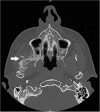

Results: In total, 63 cases of MOT of the masticatory muscles which were reported in English-based literature were included in this study. Overall, 25 female and 37 male patients could be analysed whereas one patient's gender was unknown. Complication of wisdom-tooth infection (n = 3) as well as the results of dental procedures like dental extraction (n = 7), mandibular nerve block (n = 4), periodontitis therapy (n = 1) were reported as MOT cases. From the 15 reported cases that appeared after dental treatment like extraction or local anesthesia the medial pterygoid (n = 10) was the most affected muscle. Hereof, females were more affected (n = 9) than males (n = 6). The most reported clinical symptom of MOT was trismus (n = 54), followed by swelling (n = 17) and pain (n = 13). One clinical case provided by the authors was detected.